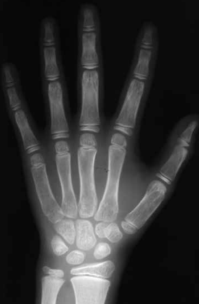

简单说,骨龄就是通过给孩子左手腕拍一张X光片,医生能评估骨骼的成熟程度。它反映了孩子生长板的“剩余潜力”。

- 对于女孩来说:骨龄达到14-15岁左右,生长潜力通常就非常有限了,也就是说骨骺基本闭合。

- 对于男孩来说:骨龄达到16-17岁左右,生长潜力通常接近尾声。